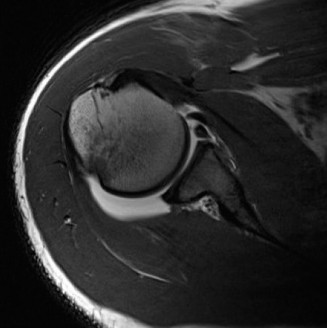

Advanced imaging is mandatory when bone loss is suspected. While Magnetic Resonance Imaging or MR Arthrogram is excellent for evaluating the capsulolabral complex, rotator cuff, and cartilage, three dimensional Computed Tomography is the gold standard for quantifying osseous defects.

The en face view of the glenoid on 3D CT with the humeral head digitally subtracted allows for precise measurement. The "best fit circle" method is commonly utilized. A circle is drawn matching the contour of the inferior and posterior glenoid, and the area or width of the missing anterior bone is calculated relative to the area or diameter of the circle. The Pico method compares the surface area of the injured glenoid to the contralateral normal glenoid, assuming the contralateral shoulder is uninjured. The humeral head must also be evaluated to calculate the glenoid track, measuring the width of the Hill-Sachs lesion and the intact anterior glenoid bone bridge.